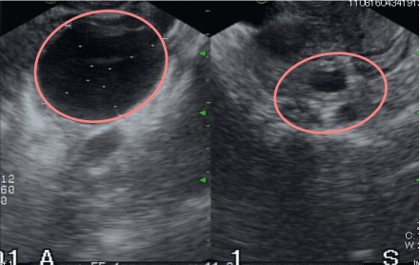

卵巣嚢腫を診断するために、医師は次のような超音波スキャンを実行することがあります。

• 経膣超音波検査。内診。超音波プローブを膣内に挿入して卵巣の画像を取得します。

• 経腹超音波検査。医師は患者の下腹部をスキャンして骨盤領域の写真を取得します。

医師が超音波検査中に卵巣嚢腫を発見した場合、嚢胞の監視を続けるために追加の超音波スキャンを要求する場合があります。